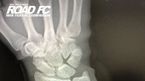

[OSEN=우충원 기자] “한국 선수들과 많은 경기 하고 싶다".지난해 12월 15일 ‘세계 랭킹 1위’ ROAD FC 아톰급 챔피언 함서희(32, 팀 매드)는 2차 방어에 성공했다. 이날 경기는 함서희가 부상에서 약 1년 만에 복귀한 시